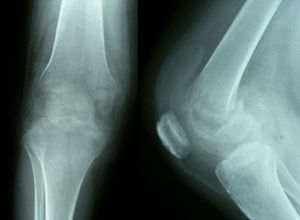

Pruebas complementarias. El estudio radiológico inicial mostró una radiolucencia difusa de la metáfisis y la epífisis femoral distal, sin líneas de fractura; el espacio articular permanecía normal (fig. 1). La resonancia magnética (RM) mostraba un extenso edema óseo en la epífisis femoral distal, más marcado en cóndilo externo, con disminución de la señal en T1 y aumento en T2, además de un pequeño derrame articular difuso (fig. 2).

Horas después de realizarse estas pruebas, la paciente sufrió una caída fortuita, refiriendo de forma inmediata dolor intenso e impotencia funcional en la rodilla derecha. El estudio radiológico urgente mostró una fractura patológica supracondílea del fémur derecho (fig. 3).